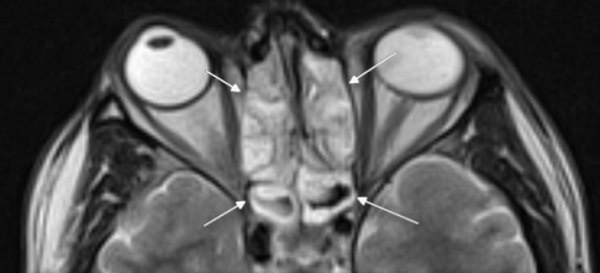

Пиоцеле (скопление гноя) задних клеток решетчатой кости